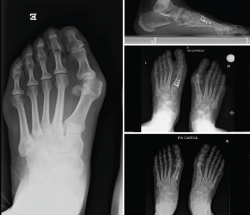

Figura 4. Caso clínico de osteotomía de apertura medial (radiología preoperatoria y control a los 6 años y 8 meses).

En las Figuras 4 y 5 se muestra un ejemplo intervenido de osteotomía de apertura y cierre.